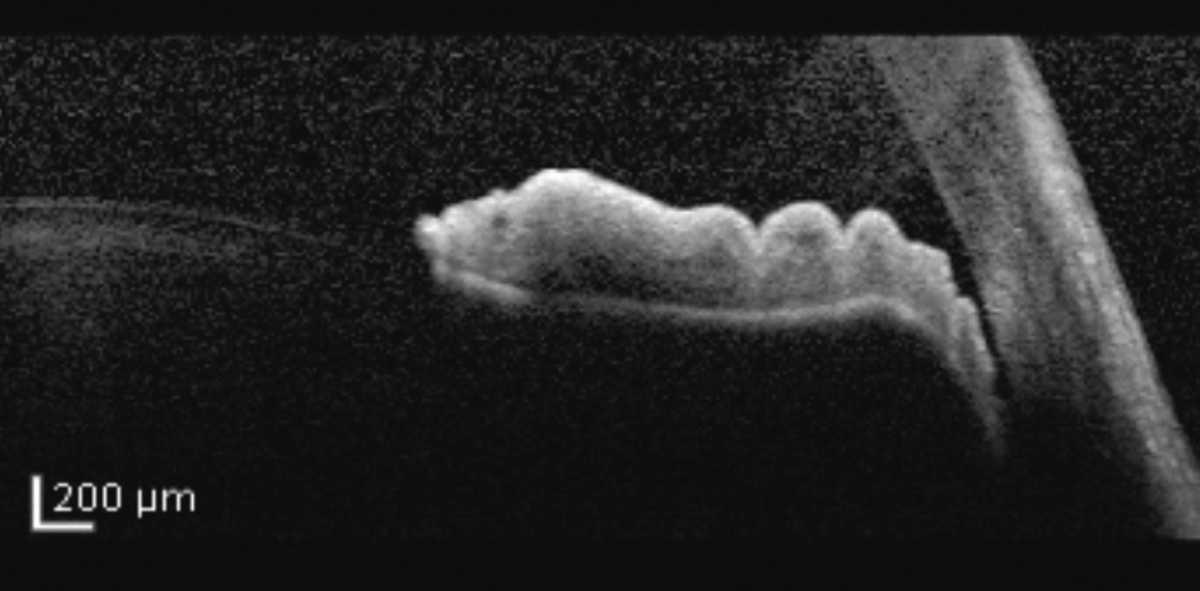

Muchos oftalmólogos integrales no están familiarizados con las características diagnósticas asociadas con el iris en meseta. En la gonioscopia, los hallazgos específicos que sugieren iris en meseta incluyen "la señal de doble joroba", en la que se puede ver un efecto de ondulación del iris periférico.

"Si la profundidad de la cámara anterior es profunda en el centro y estrecha en la periferia, existe la posibilidad de que el paciente pueda tener una configuración de iris en meseta", dice el Dr. James C. Tsai, MBA, presidente de New York Eye & Ear Infirmary del Mount Sinai. "El tipo clásico de sospecha de cierre angular por bloqueo pupilar es un paciente con una profundidad central de la cámara anterior reducida, así como una periferia estrecha." Observado con mucha frecuencia en pacientes jóvenes con ángulos estrechos, la configuración del iris en meseta presenta una posición anterior anormal del cuerpo ciliar. La entidad se caracteriza por un cierre de ángulo aposicional con una configuración de iris plano en comparación con el arqueamiento anterior del iris en el paciente con sospecha de glaucoma de ángulo cerrado más típico. Cuando las pupilas están dilatadas, el ángulo se apiña por el agrupamiento focal del iris periférico, lo que provoca un aumento de la presión intraocular y un ataque de cierre de ángulo".

| El "signo de la doble joroba" sugiere iris en meseta, mostrando un efecto ondulado del iris periférico. La identificación precisa de la configuración del iris en meseta influye en la planificación del tratamiento, dicen los especialistas en glaucoma. |

| El iris en meseta se presenta con una posición anterior anormal del cuerpo ciliar con la raíz del iris empujada más periféricamente hacia el ángulo. |